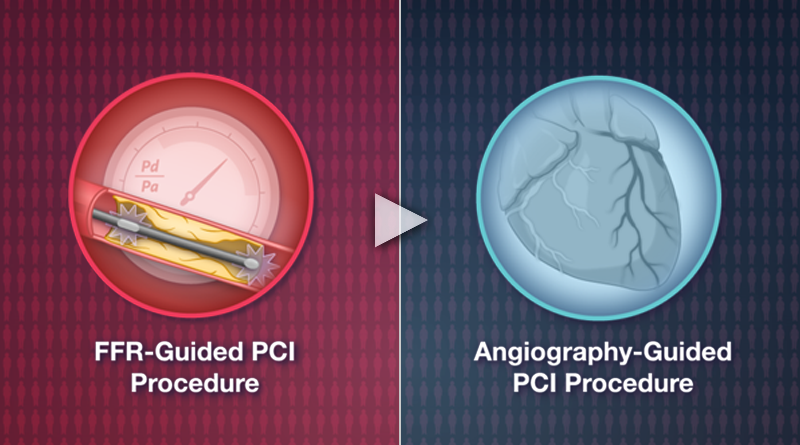

Running series of animated visual abstracts, Quick Takes, created for The New England Journal of Medicine as part of a team of illustrators, medical writers, and scientists. These short, iconographic animations aim to succinctly describe clinical trials and increase the awareness and understanding of important research findings.

Adopting The Journal’s visual style and asset library, I am responsible for the entire production process including narration editing, storyboarding, layout, illustration, and animation.